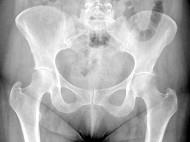

女,根据其正常骨盆影像图像,判断其最可能的年龄?(?)A.28岁左右B.18岁左右C.38岁左右D.78岁左右E.58岁左右

问题 女,根据其正常骨盆影像图像,判断其最可能的年龄?(?)

选项 A.28岁左右 B.18岁左右 C.38岁左右 D.78岁左右 E.58岁左右

答案 E